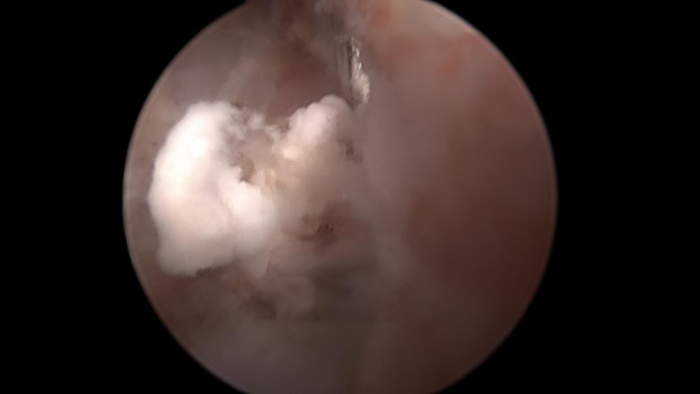

门诊医生立即为黄阿姨办理了住院,并于当天晚上完成急诊手术,通过3个0.5cm小切口在关节镜下解决了病因。镜下可见冈上肌腱内冒出牙膏状钙化沉积物,彻底清理后缝合肩袖破口。